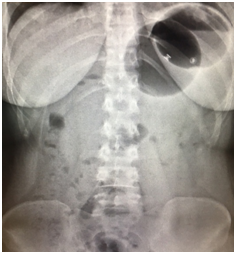

A first and second balloon was ingested successfully by 74 subjects. The mean time for ingestion procedures (swallowing of the capsule and inflation of the balloon) was 9min (range: 5-22min). All balloons were removed by upper GI endoscopy, under conscious sedation without tracheal intubation. At the time of withdrawal, we found 2 subjects with 1 balloon deflated (these 2 subjects came for withdrawal after 4months, and the balloons were expelled through the stools). 10 gastric superficial erosion lesions were observed in 10 subjects, probably in relation with using NSAIDs and without proton pump inhibitor (PPI). The balloons were removed without any difficulty in all cases. Stomach pain/cramping was the most common adverse event occurring in 65 (87%) subjects, being treated with oral antispasmodic medical therapy, and 18 (24%) subjects reported Nausea, treated by oral domperidone. All reported adverse events (AEs) were mild to moderate at most. The number of AEs was similar with one and two balloons. No reported cases of removing balloons before 12weeks. This pilot study showed significant decrease of weight and body mass index at 12weeks, with high rate of successfully swallowing and transient side effects induced by up to two balloons (Figures 1-5).